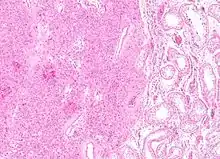

| Histopathology of a Leydig cell tumor, high magnification, H&E stain, showing typical features.[1] | |

Intermediate magnification micrograph of a Leydig cell tumour. H&E stain.

High magnification micrograph of a Leydig cell tumour. H&E stain.